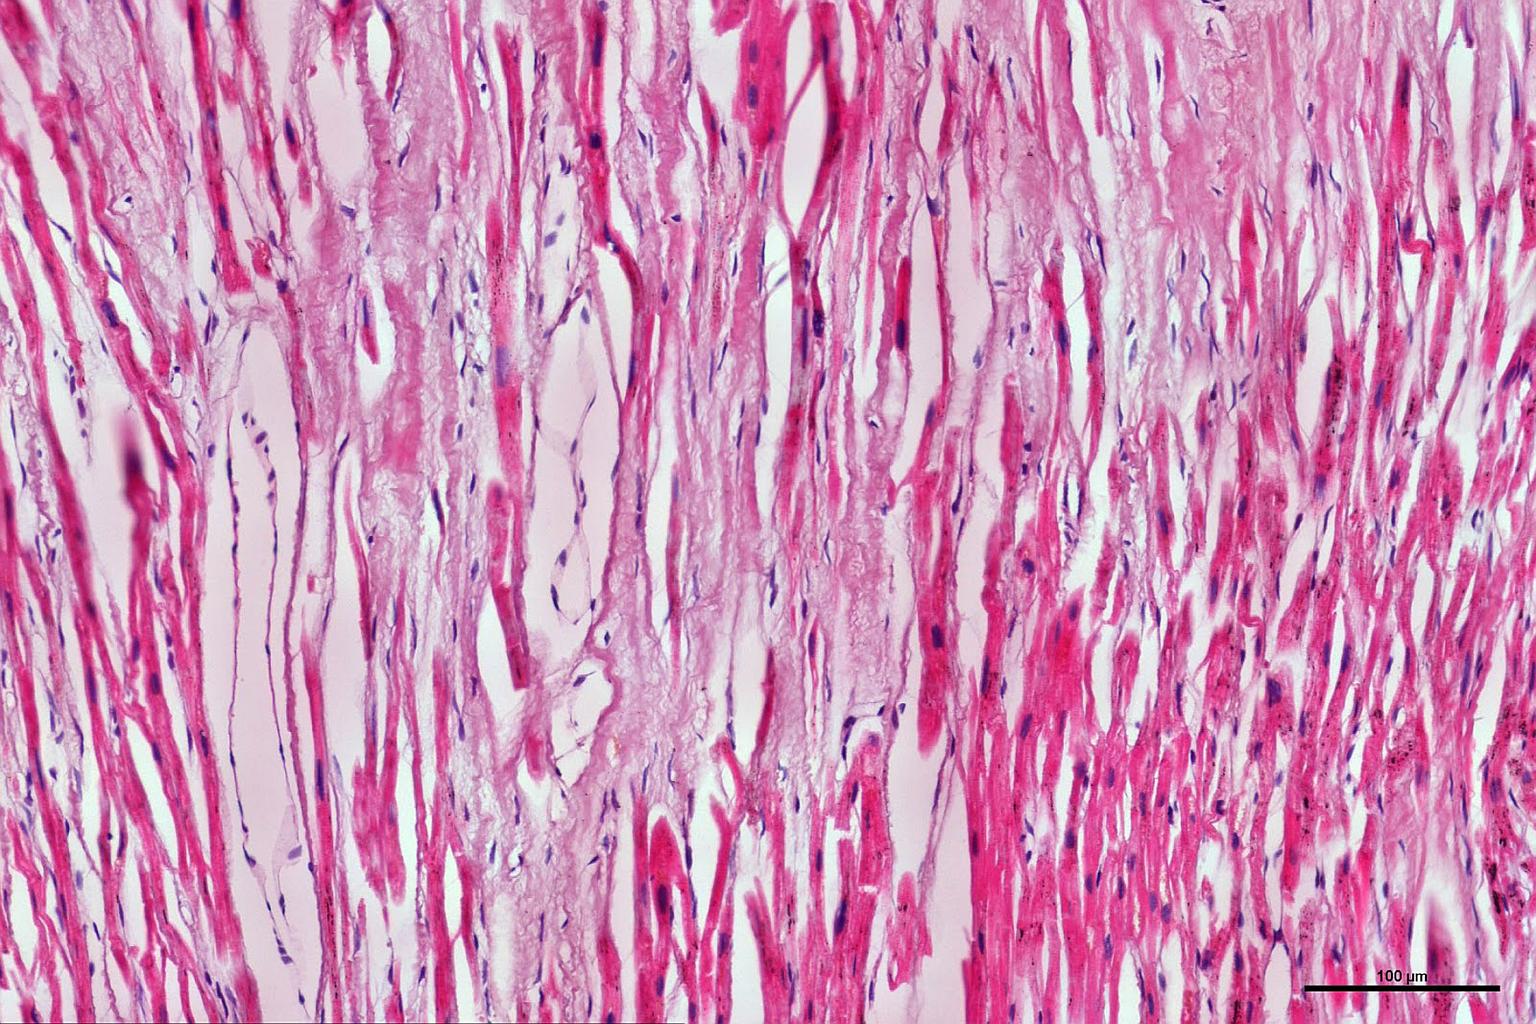

A cross-sectional view of the heart muscle.

PHOTO: NUS YONG LOO LIN SCHOOL OF MEDICINE